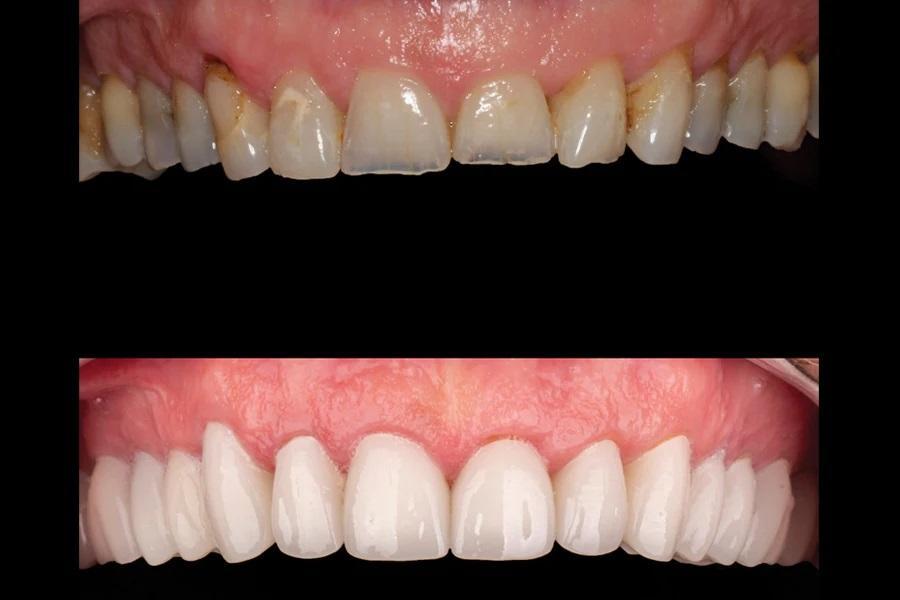

Биомеханика: Кариозные поражения: 1.6–1.3, 2.4, 2.5, 3.7, 3.5, 3.4, 4.4. Крупные реставрации: 1.7–1.3, 2.5–2.7, 3.7–3.5, 4.5, 4.6. Три зуба под коронками; эндодонтическое лечение ранее — 3.6 и 3.5. Зуб 3.7 — значительная утрата тканей. На передних зубах — умеренно-тяжелая атриция и эрозия. Ряд реставраций на 1.4, 2.3, 2.4, 3.7 — неудовлетворительное состояние/неудачные (Фото 5 и Фото 6).

Фото 5. Окклюзионный вид верхнечелюстной дуги до лечения. Обратите внимание на большие реставрации, истирание и эрозию.

При реабилитации одной дуги точный диагноз и понимание ожиданий пациента критически важны для составления плана. После верификации ОЖП окклюзию необходимо было скорректировать для долговечности реставраций. Возможен был ортодонтический подход (увеличение ВРО за счет экструзии моляров одной из дуг, интрузии 3.3–3.2–3.1–4.1–4.2 и/или прогнатизации 1.2–2.2), но пациент категорически отказался от ортодонтии. Поскольку верхние зубы имели крупные дефектные реставрации и были структурно ослаблены, полноокрывающие коронки на весь верхний ряд стали разумным решением: они поддерживали ослабленные зубы (снижение биомеханического риска), увеличивали ВРО для коррекции ОЖП и обеспечивали желаемую эстетику (Фото 14 – Фото 17).

Фото 16. Верхняя дуга до (верх) и после (низ) лечения.